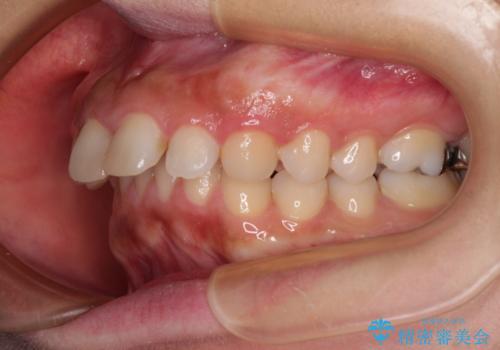

- 上の前歯が出っ歯と突出した口元を気にして来院された患者様です。

上顎歯列全体が前方に飛び出している印象であったので、上顎左右の第一小臼歯2本を抜歯し、ワイヤー装置にて抜歯矯正を行うこととしました。